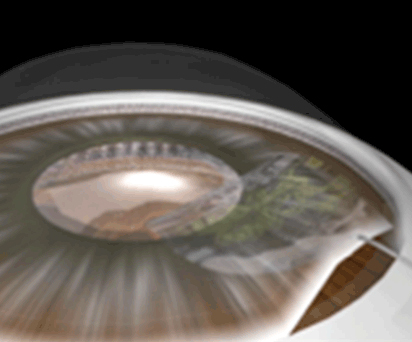

私の白内障の術式をシェーマで説明を致します。

前嚢切開は前嚢鑷子を用いて、4-5mm経で正円に行っております。

白内障をプレチョッパーを用いて4分割した後、白内障を超音波で乳化させて吸引します。(超音波乳化吸引術)

切開創を拡げることなく、眼内レンズを小さく折りたたんでインジェクターを用いて、眼内レンズを眼内にインサートします。これで白内障手術は終了です。